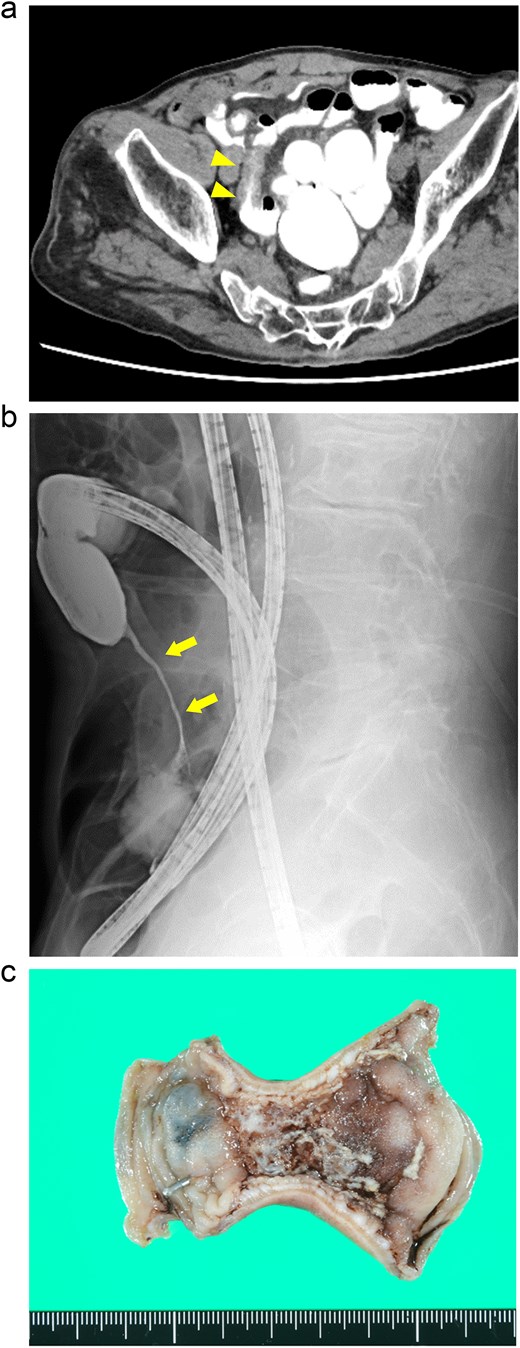

A 76-year-old man presented with a gradual onset of intermittent epigastric and left abdominal pain. Three months prior, he experienced similar pain, and computed tomography (CT) revealed hepatic portal venous gas (HPVG) without mesenteric ischemia or bowel strictures. The patient’s symptoms resolved with conservative treatment, none of the CT features during follow-up. His vital signs were stable, and laboratory test results were normal, including a white blood cell (WBC) count of 8800/μl, C-reactive protein (CRP) concentration of 0.02 mg/dl, hemoglobin (Hb) level of 12.5 g/dl, and lactate (Lac) concentration of 0.7 mmol/l. CT enterography revealed a segmental stricture with wall thickening in the distal ileum (Fig. 1a). Double-balloon endoscopy (DBE) revealed a circumferential ulcer and segmental stricture in the distal ileum. Fluoroscopy during DBE confirmed segmental, smooth luminal narrowing in the distal ileum (Fig. 1b).

Case 1: (a) CT enterography with water-soluble contrast agent. The arrowheads indicate a segmental stricture with wall thickening in the distal ileum. (b) Fluoroscopy during double-balloon endoscopy. The arrows indicate a segmental, smooth luminal narrowing in the distal ileum. (c) Macroscopic view of the resected specimen. Circumferential ulceration is visible in the affected area.

Exploratory laparoscopy revealed a 10-cm-long segmental bowel stricture with wall thickening 50 cm from the ileocecal valve, which was resected. The pathological specimen revealed a circumferential ulcer with granulation tissue at the stenotic site, accompanied by edematous mucosa and fibrotic submucosa in the surrounding areas. No signs of tumors or inflammatory bowel disease (IBD) were noted (Fig. 1c). The postoperative course was uneventful, and the patient was discharged on the ninth postoperative day. By the 10-month follow-up, he had not had any recurrences of abdominal symptoms.